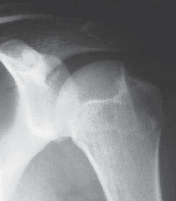

Advanced imaging is non-negotiable in the modern era of instability surgery. Standard radiographic series must include an AP view in internal rotation (to assess for Hill-Sachs lesions and greater tuberosity fractures), a true AP of the glenohumeral joint (Grashey view), and a West Point axillary view to critically evaluate the anteroinferior glenoid rim for bony avulsions or attritional wear. When bony deficiencies are suspected based on plain films or clinical history (e.g., instability during sleep, apprehension at low abduction angles), a 3D reconstructed Computed Tomography (CT) scan with humeral head subtraction is the gold standard. This allows for precise, volumetric quantification of glenoid bone loss utilizing the best-fit circle method. Magnetic Resonance Imaging (MRI), preferably with intra-articular gadolinium arthrography (MRA), is indispensable for evaluating the integrity of the labrum, identifying ALPSA (Anterior Labroligamentous Periosteal Sleeve Avulsion) or GLAD (Glenolabral Articular Disruption) lesions, and ruling out concomitant rotator cuff tears or capsular ruptures.

The fundamental pathoanatomic lesion driving traumatic anteroinferior instability is the Bankart lesion, defined as the traumatic avulsion of the anteroinferior labrum and its attached capsule from the anterior glenoid rim. This lesion is ubiquitous, present in approximately 90% of all traumatic glenohumeral dislocations. Recurrent dislocation episodes invariably lead to progressive plastic deformation of the middle and inferior glenohumeral ligaments, exacerbating capsular redundancy and compromising the critical "sling" mechanism designed to restrict anterior translation. Furthermore, recurrent instability drastically increases the incidence of secondary osseous injuries, including the Hill-Sachs lesion (a posterosuperior humeral head impaction fracture) and the bony Bankart lesion (attritional bone loss or fracture of the anterior glenoid rim). In older demographics, the pathoanatomic profile shifts; a traumatic dislocation in a patient over the age of 40 must be viewed with a high index of suspicion for concomitant rotator cuff pathology, necessitating a meticulous strength examination and advanced soft-tissue imaging.